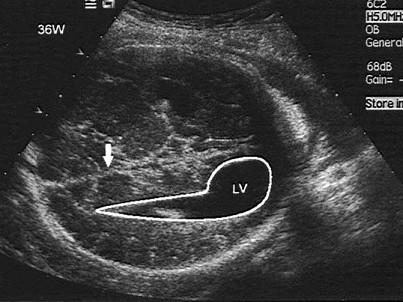

如图,36周胎儿,最可能的诊断是?(?)A.正常声像图B.脑疝C.脑积水D.泪滴状侧脑室E.以上都不是

问题 如图,36周胎儿,最可能的诊断是?(?)

选项 A.正常声像图 B.脑疝 C.脑积水 D.泪滴状侧脑室 E.以上都不是

答案 D